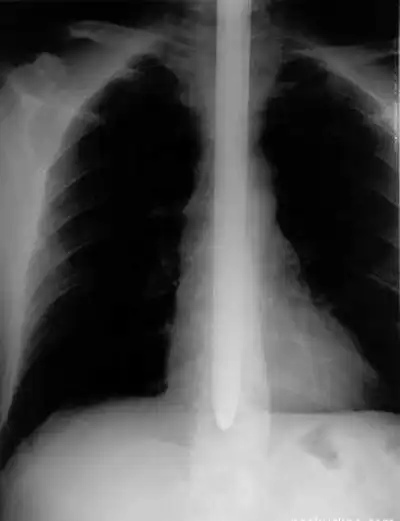

О человеке с так называемой военной выправкой и нарочито правильной осанкой злые языки скажут: он проглотил вертикальный несгибаемый предмет. Сразу представишь себе арматурный прут. И рентгеновский снимок военной выправки.

Такой:

После тренировок у шпагоглотателя притупляются ощущения в глотке и пищеводе. Циркач начинает учиться задирать голову так, чтобы глотка и пищевод уложились в прямую линию. Только при особенной, неповторимой осанке меч или шпага входит в пищевод, не касаясь чувствительных участков тракта, и даже в желудок фокусника.